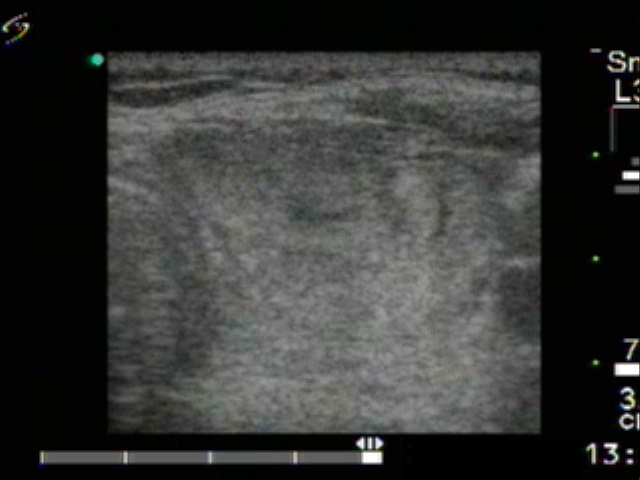

First session of therapy (first row of images)

Clinical presentation. A 65-year-old colleague was regularly checked for more than a decade because of a nodule in the left lobe. At first visit the size of the nodule was 15x11x22 mm. Except for cosmetics the nodule did not cause complaint.

Ultrasonography: the thyroids were echonormal. A large nodular area replaced the normal parenchyma in the left lobe. The lesion was composed of a larger echonormal nodule presenting halo sign and a smaller hypoechogenic one.

Aspiration cytology of the hypoechogenic nodule resulted in benign cystic-colloid goiter.

The colleague wished to avid surgery and decided to undergo sclerotherapy instead. 5 sessions of sclerotherapy were performed. On the first occasesion we injected 3 mL ethanol.